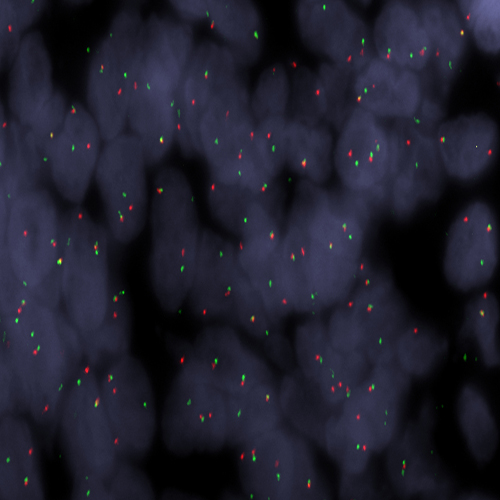

Ewing Sarcoma stained using EWSR1 (22q12) Break – XL for BOND (KBI-XL019).

The EWSR1 (22q12) Break - XL for BOND FISH probe detects genomic translocations involving the EWSR1 gene in FFPE tissues. EWSR1 (22q12) Proximal - XL and EWSR1 (22q12) Distal - XL are optimized to detect genomic regions proximal and distal to break points in the EWSR1 gene region.

When combined, both probes are used to detect translocations involving the EWSR1 gene at 22q12.